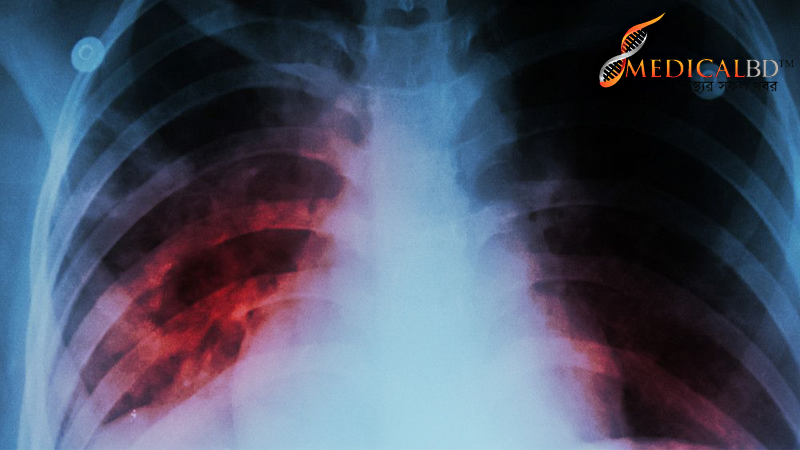

বিশ্ব স্বাস্থ্য সংস্থা বলছে, বাংলাদেশে বছরে প্রায় ৬৬ হাজার মানুষ যক্ষ্মা রোগে মারা যাচ্ছে। অর্থাৎ দিনে ১৮০ জনের মৃত্যু হচ্ছে যক্ষ্মায়। যক্ষ্মায় আক্রান্ত ৩৩ শতাংশ রোগী এখনো চিকিৎসার বাইরে। দেশে যক্ষ্মা রোগ শনাক্তকরণ আধুনিক যন্ত্রের স্বল্পতা আছে।

সংবাদ সম্মেলনে বৈশ্বিক ও দেশের যক্ষ্মা পরিস্থিতি তুলে ধরেন জাতীয় যক্ষ্মা নিয়ন্ত্রণ কর্মসূচির চিকিৎসা কর্মকর্তা নাজিস আরেফিন। তিনি বলেন, দেশে যক্ষ্মা এখনো জনস্বাস্থ্য সমস্যা হিসেবে আছে। বিশ্ব স্বাস্থ্য সংস্থার সর্বশেষ বৈশ্বিক যক্ষ্মা প্রতিবেদনের তথ্য উদ্ধৃত করে তিনি বলেন, ২০১৬ সালে বাংলাদেশে যক্ষ্মায় ৬৬ হাজার মানুষের মৃত্যু হয়। আর ৩ লাখ ৬০ হাজার মানুষ নতুন করে যক্ষ্মার জীবাণুতে আক্রান্ত হয়। আর ওষুধ প্রতিরোধী যক্ষ্মায় (এমডিআর টিবি) আক্রান্তের সংখ্যা ছিল ৫ হাজার ৩০০। বিশ্ব স্বাস্থ্য সংস্থা যক্ষ্মার প্রকোপ এবং ওষুধ প্রতিরোধী যক্ষ্মার প্রকোপ বেশি এমন দেশের তালিকা তৈরি করেছে। দুটি তালিকাতেই বাংলাদেশের নাম আছে।সংবাদ সম্মেলনের শুরুতে বলা হয়, যক্ষ্মা নির্ণয়, সব ধরনের পরীক্ষা-নিরীক্ষা ও ওষুধ বিনা মূল্যে দেওয়া হয়। ব্র্যাকসহ ২৬টি এনজিও যক্ষ্মা নিয়ন্ত্রণে সরকারকে সহায়তা করছে।